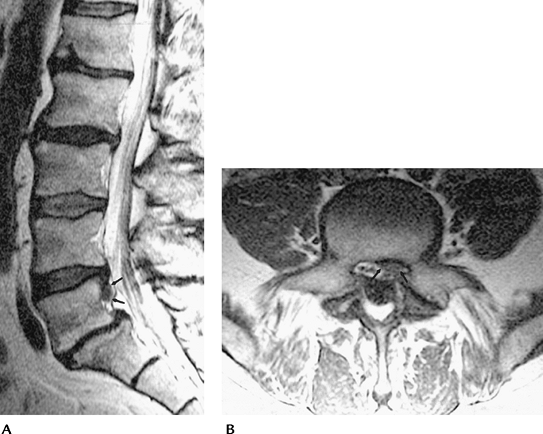

![]() |

FIGURE 3-54 Lumbar disc sequestration. Sagittal T2-weighted (A) image demonstrates a rounded focal 1-cm region of soft tissue signal intensity posterior to the upper L5 vertebral body (arrows) separate from the parent disc. Axial T1-weighted (B) image demonstrates disc material in the left lateral recess of L5 (arrows).